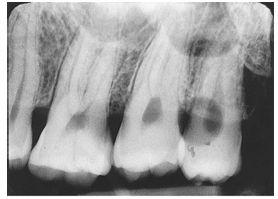

What is the problem with this DEVELOPER SPOTS X-ray?

Appears with black or dark spots, Developer comes in contact with film before processing

How would you resolve this DEVELOPER SPOTS X-ray?

Use a clean work area in the darkroom